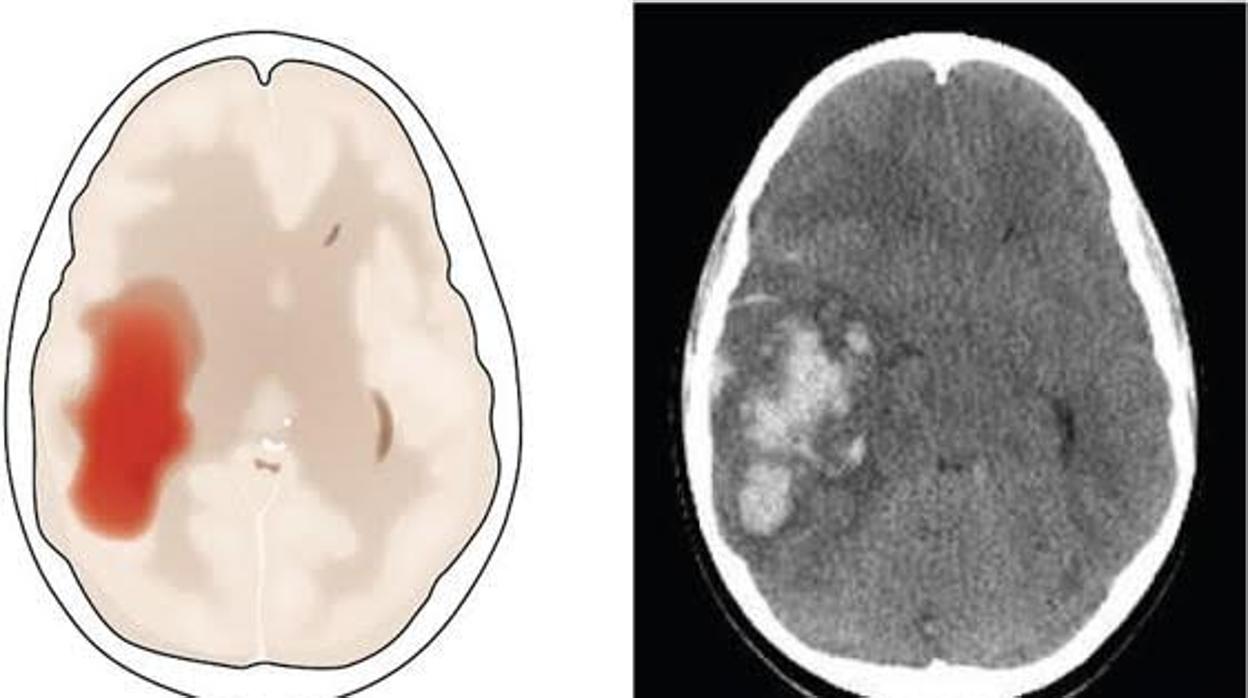

Ictus hemorrágico ARCHIVO